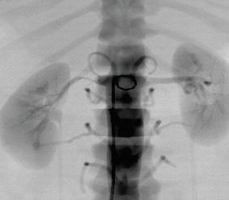

腎動脈介入手術(shù)模塊

可練習(xí)腎動脈支架手術(shù)的完整過程:造影診斷、導(dǎo)絲通過、導(dǎo)引導(dǎo)管的放置、保護(hù)傘的放置、預(yù)擴張、自擴張支架放置、后擴張、以及再造影等